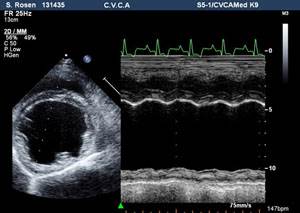

ЭХОКГ (эхокардиография сердца). Метод позволяет поставить окончательный диагноз и оценить сердечную сократимость, толщину сердечной стенки, степень увеличения отделов сердца.